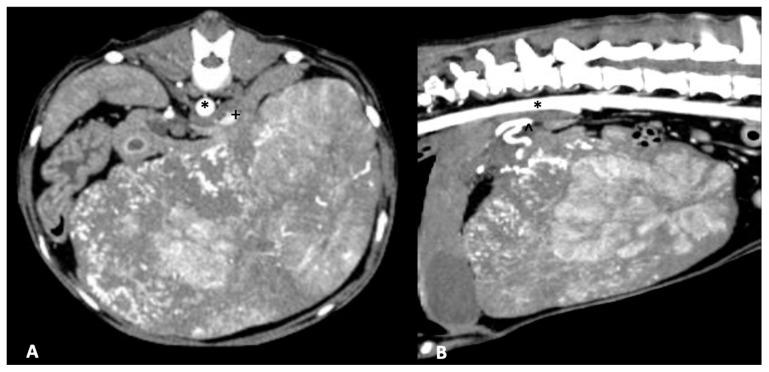

Primary hepatic neoplasia is uncommonly reported in dogs. Hepatocellular carcinoma (HCC) is the most frequent neoplasia identified in dogs and considerable effort has been committed towards identifying definitive and palliative treatment options. HCC is well recognized in humans as a sequelae of liver disease such as hepatitis or cirrhosis, while in dogs a similar link has failed to be fully elucidated. Management of HCC in people may be curative or palliative dependent on staging and transplant eligibility. Despite differences in etiology, there is substantial similarity between treatment options for liver neoplasia in human and veterinary medicine. The below summary provides a comparative discussion regarding hepatic neoplasia in dogs and people with a specific focus on HCC. Diagnosis as well as descriptions of the myriad treatment options will be reviewed.

原发性肝肿瘤在犬类中报道较少。肝细胞癌(HCC)是犬类中最常见的肿瘤,人们已付出相当大的努力来确定确定性和姑息性治疗方案。HCC在人类中被公认为是肝炎或肝硬化等肝脏疾病的后遗症,而在犬类中,类似的联系尚未完全阐明。人类HCC的治疗可能是治愈性的或姑息性的,这取决于分期和移植资格。尽管病因不同,但人类和兽医学中肝脏肿瘤的治疗选择有很大的相似性。以下总结对犬类和人类的肝肿瘤进行了比较讨论,特别关注HCC。将对诊断以及众多治疗选择进行综述。